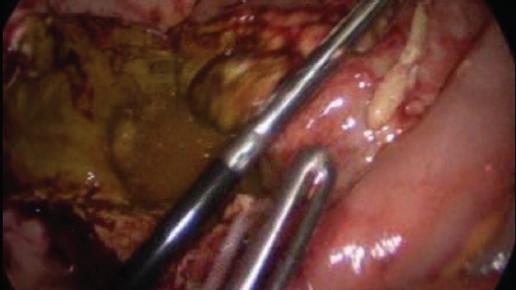

Se decidió realizar exploración quirúrgica de urgencia por abordaje laparoscópico, encontrando material intestinal y purulento libre en la cavidad (Fig. 2), con el ciego perforado hacia la vejiga, observándose el globo de la sonda transuretral (Fig. 3). Se realizó hemicolectomía derecha (Fig. 4) con ileostomía terminal, cierre primario de la perforación vesical en tres planos (Figs. 5 y 6) y colocación de drenaje. La paciente se mantuvo en vigilancia posoperatoria en terapia intensiva, resolvió el cuadro de sepsis abdominal y fue egresada al sexto día a piso para continuar su recuperación a cargo de los servicios de nefrología y cirugía general. En el día 15 de posoperatorio se evidenció una nueva colección intraabdominal en la corredera parietocólica derecha, la cual se trató mediante drenaje percutáneo y antibiótico por vía intravenosa, resolviéndose sin complicaciones. Continuó con evolución tórpida por sus patologías de base, requiriendo múltiples sesiones de hemodiálisis, y finalmente falleció por complicaciones asociadas a la enfermedad renal.